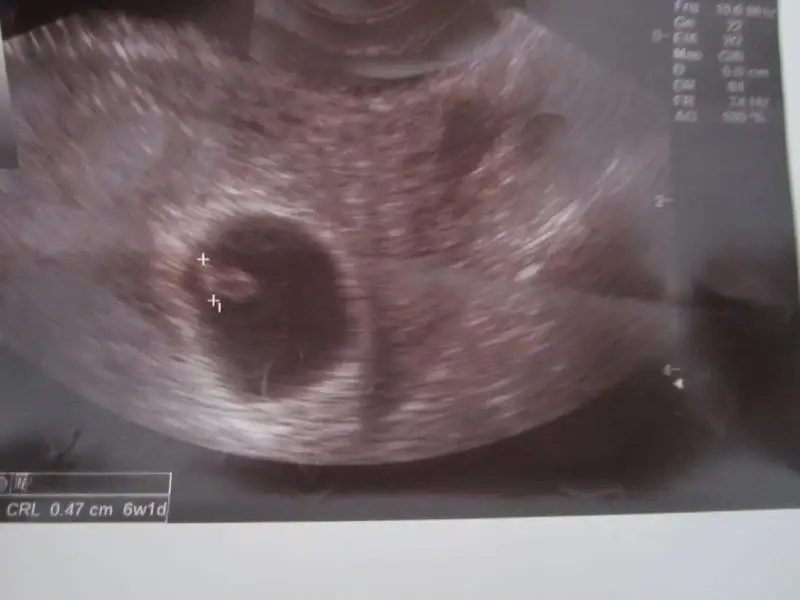

bebegin7-8 haftalıkkenki usg resimine direkt baktıgınızda;

bebek kesenin soluna yakınsa bebek erkek,

sagına yakınsa kız.

Bence bebek kız. Allah gönlünüze göre versin inşallah.Kızlar banada bir yorum yapabilirmisiniz? Bu 6 haftalık ilk vajinal ultrason resmim Eki Görüntüle 777393 Buda 8 haftalık karından bakılan ultrason resmimEki Görüntüle 777395 Burdaki okuduğum bir seyi doktorumada sordum 8haftalık ultrasonda dakıkada kalp atış hızı 140 cıvarı oldgnu soyledı ama bunun cinsiyetle bir alakası olmadıgınıda söyledi:)hadi bana yorum yapınsizce bebeğim kızmı erkekmi?